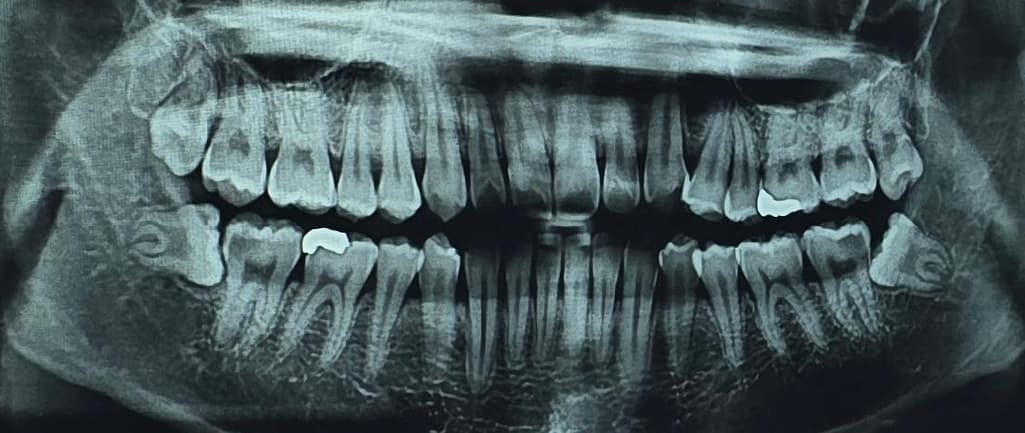

아래 양 쪽 모두 한쪽은 신경치료, 한쪽은 충치치료를 먼저 받고 사랑니 발치를 하자고 하셨는데, 발치할 때 신경치료한 부분에 문제는 없겠죠..??

그리고 누워있는 매복 사랑니는 뺄 때 힘들다고 하는데, 통증이 심하다거나 빼는 과정이 어려운 사랑니인지 궁금합니다..! 20대 초반이고 겁쟁이라서 질문드려요..감사합니다

쉬운 발치는 아니지만 그렇다고 엄청 어려운 발치는 아닐것같습니다. 20대 초반이시라면 사랑니 전문 치과에 가시면 쉽게 발치해줄것같습니다.

사랑니가 기울어져 나있고 뿌리가 휘어져 있어. 발치를 하는 과정이 힘들 수도 있습니다. 하지만 20대라면 뼈가 단단한 편이 아니기 때문에 사랑니가 나오는데 수월할 수 있습니다. 사랑니를 발치하고 신경치료를 하는 치료는 어려운 치료는 아닙니다.

신경과 가깝고 옆 어금니와 겹쳐 있어서 주의할 필요는 있으나 다행히 뿌리가 안쪽으로 수렴하는 형태이고, 아직 20대라 젊어서 아주 어려운 케이스는 아닐 것 같습니다. 발치 시 마취만 잘되면 통증 없습니다.

사랑니는 누워있는 각도가 큰 편이라 난이도 또한 높은 편입니다. 구강외과 전문의한테 뽑는 게 좋아보입니다.